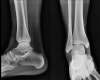

Cf) 경골하 부골(Os subtibiale : distal to tip of medial malleolus)

Cf) 비골하 부골(Os subfibulare : distal to tip of lateral malleolus)